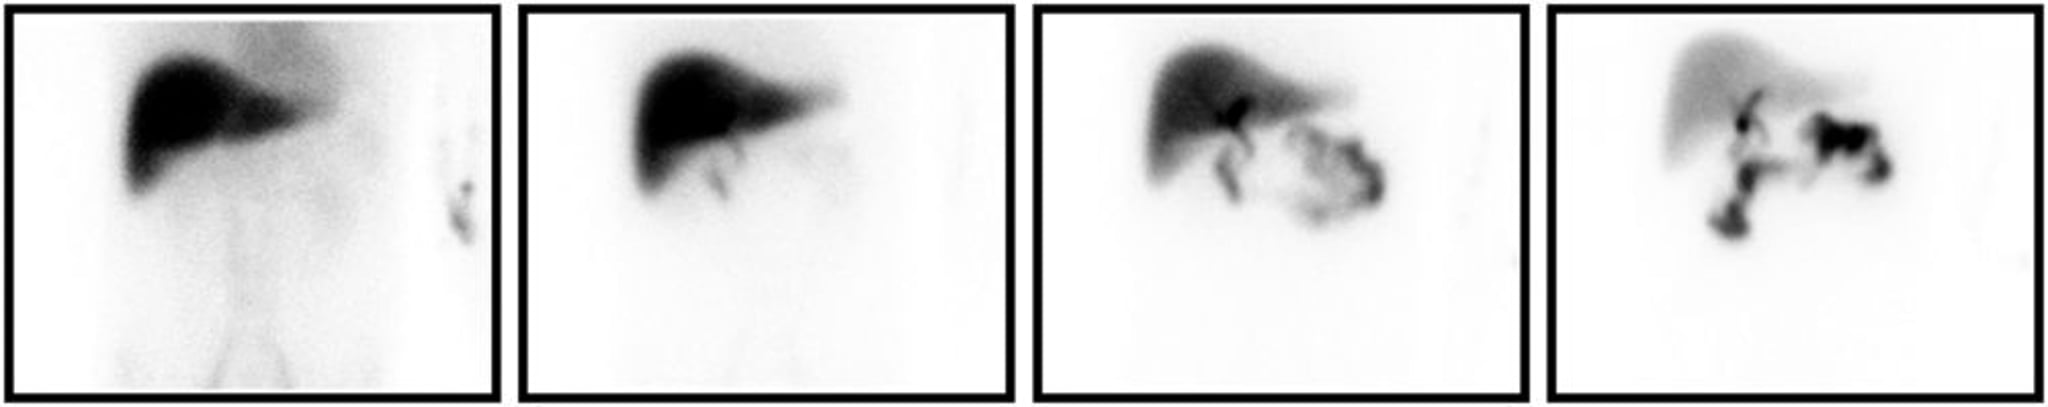

Gammagrafía con HIDA

Gammagrafía con HIDA compatible con colecistitis. Se muestran de izquierda a derecha las imágenes adquiridas a los 5, 15, 30 y 60 minutos después de la inyección del marcador radiactivo. Incluso en los momentos tardíos, la vesícula biliar no se llena.